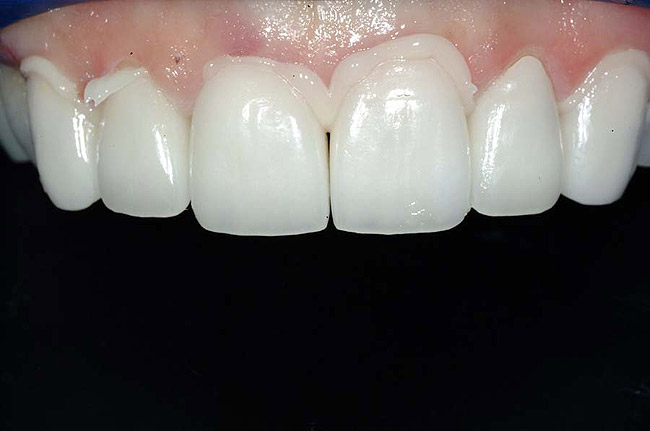

Figure 12 Occlusion was adjusted using a fine diamond bur, and the lingual aspects of the teeth were finished and polished, rendering a very satisfactory esthetic result.

Figure 13 Final postoperative view of the definitively cemented porcelain laminate veneer restorations

The cementation process for the placement of porcelain laminate veneers is a significant-yet often under appreciated-part of this esthetic restorative process. Understanding the characteristics of the cement selected, as well as the manner in which associated aspects of relevant protocol can impact the predictability of both cement and veneer performance, can greatly enhance the likelihood of realizing clinical success (Figure 13');" rem="#ip:figure12 and Figure 13">Figure 12 and Figure 13). This article has discussed factors that influence cement selection for, and the cementation of, porcelain laminate veneers and why those considerations are significant to the long-term clinical success of these restorations.